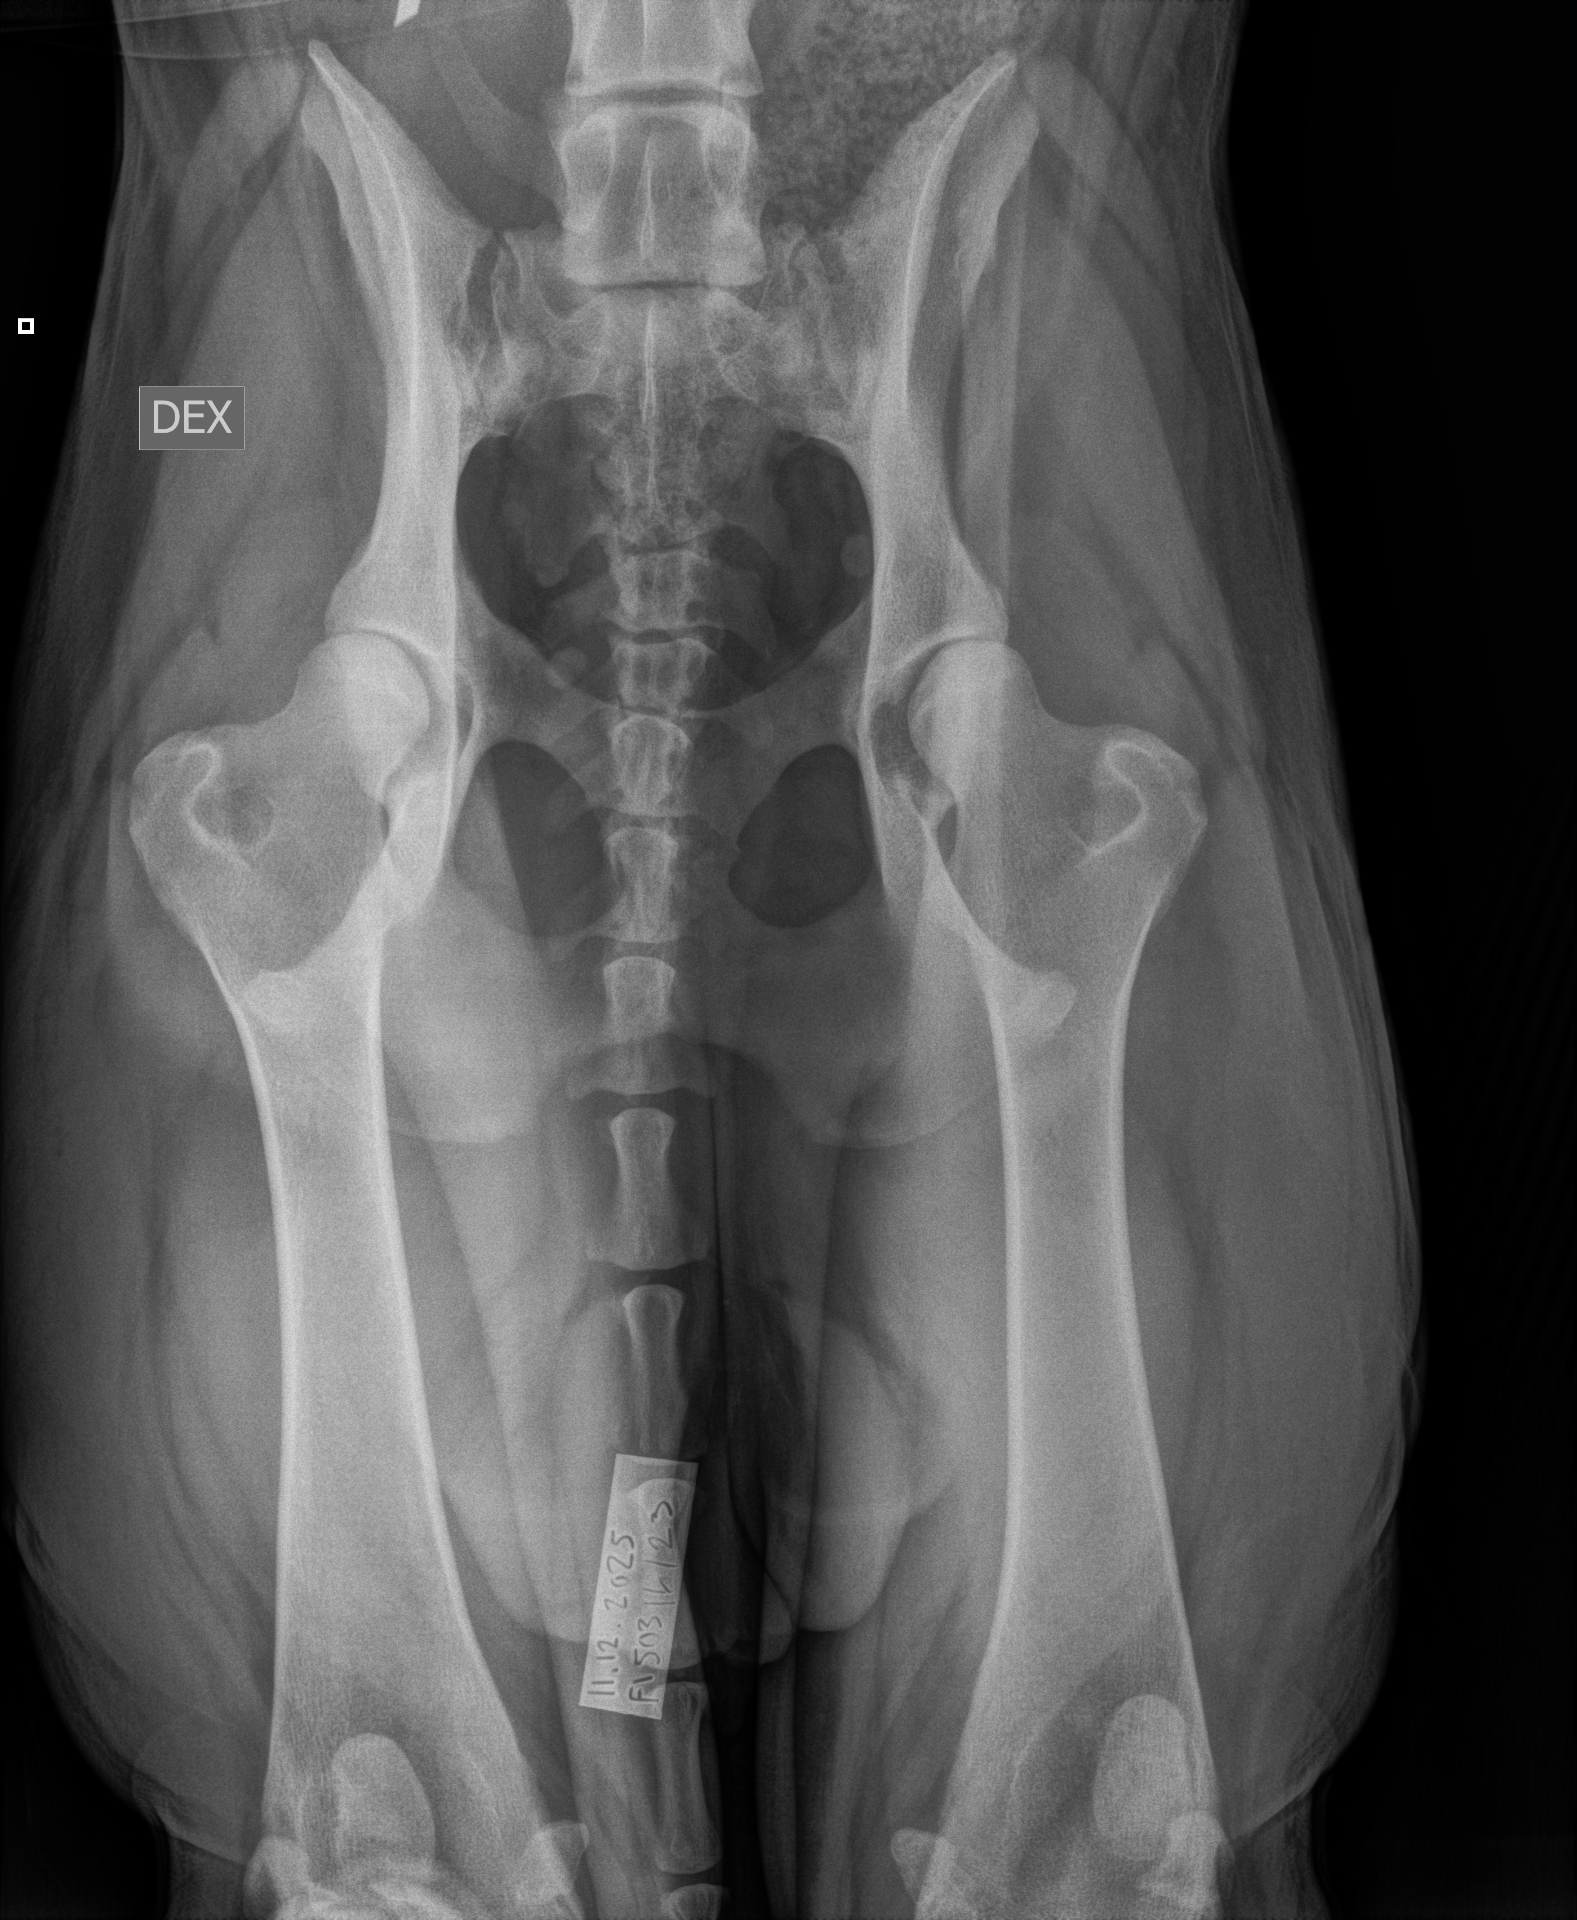

| 14.12.2025 | selkälausunto nikamien epämuotoisuus selän spondyloosi välimuotoinen lanne-ristinikama | VA1 (Aste 1, lievä), lukumäärä: 1 SP0 (Puhdas) LTV0 (Normaali) |